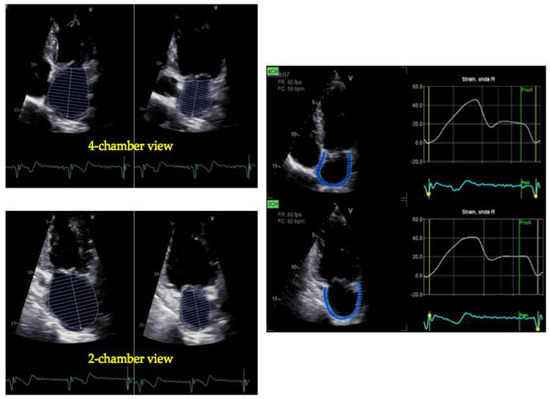

4. Peak Atrial Longitudinal Strain